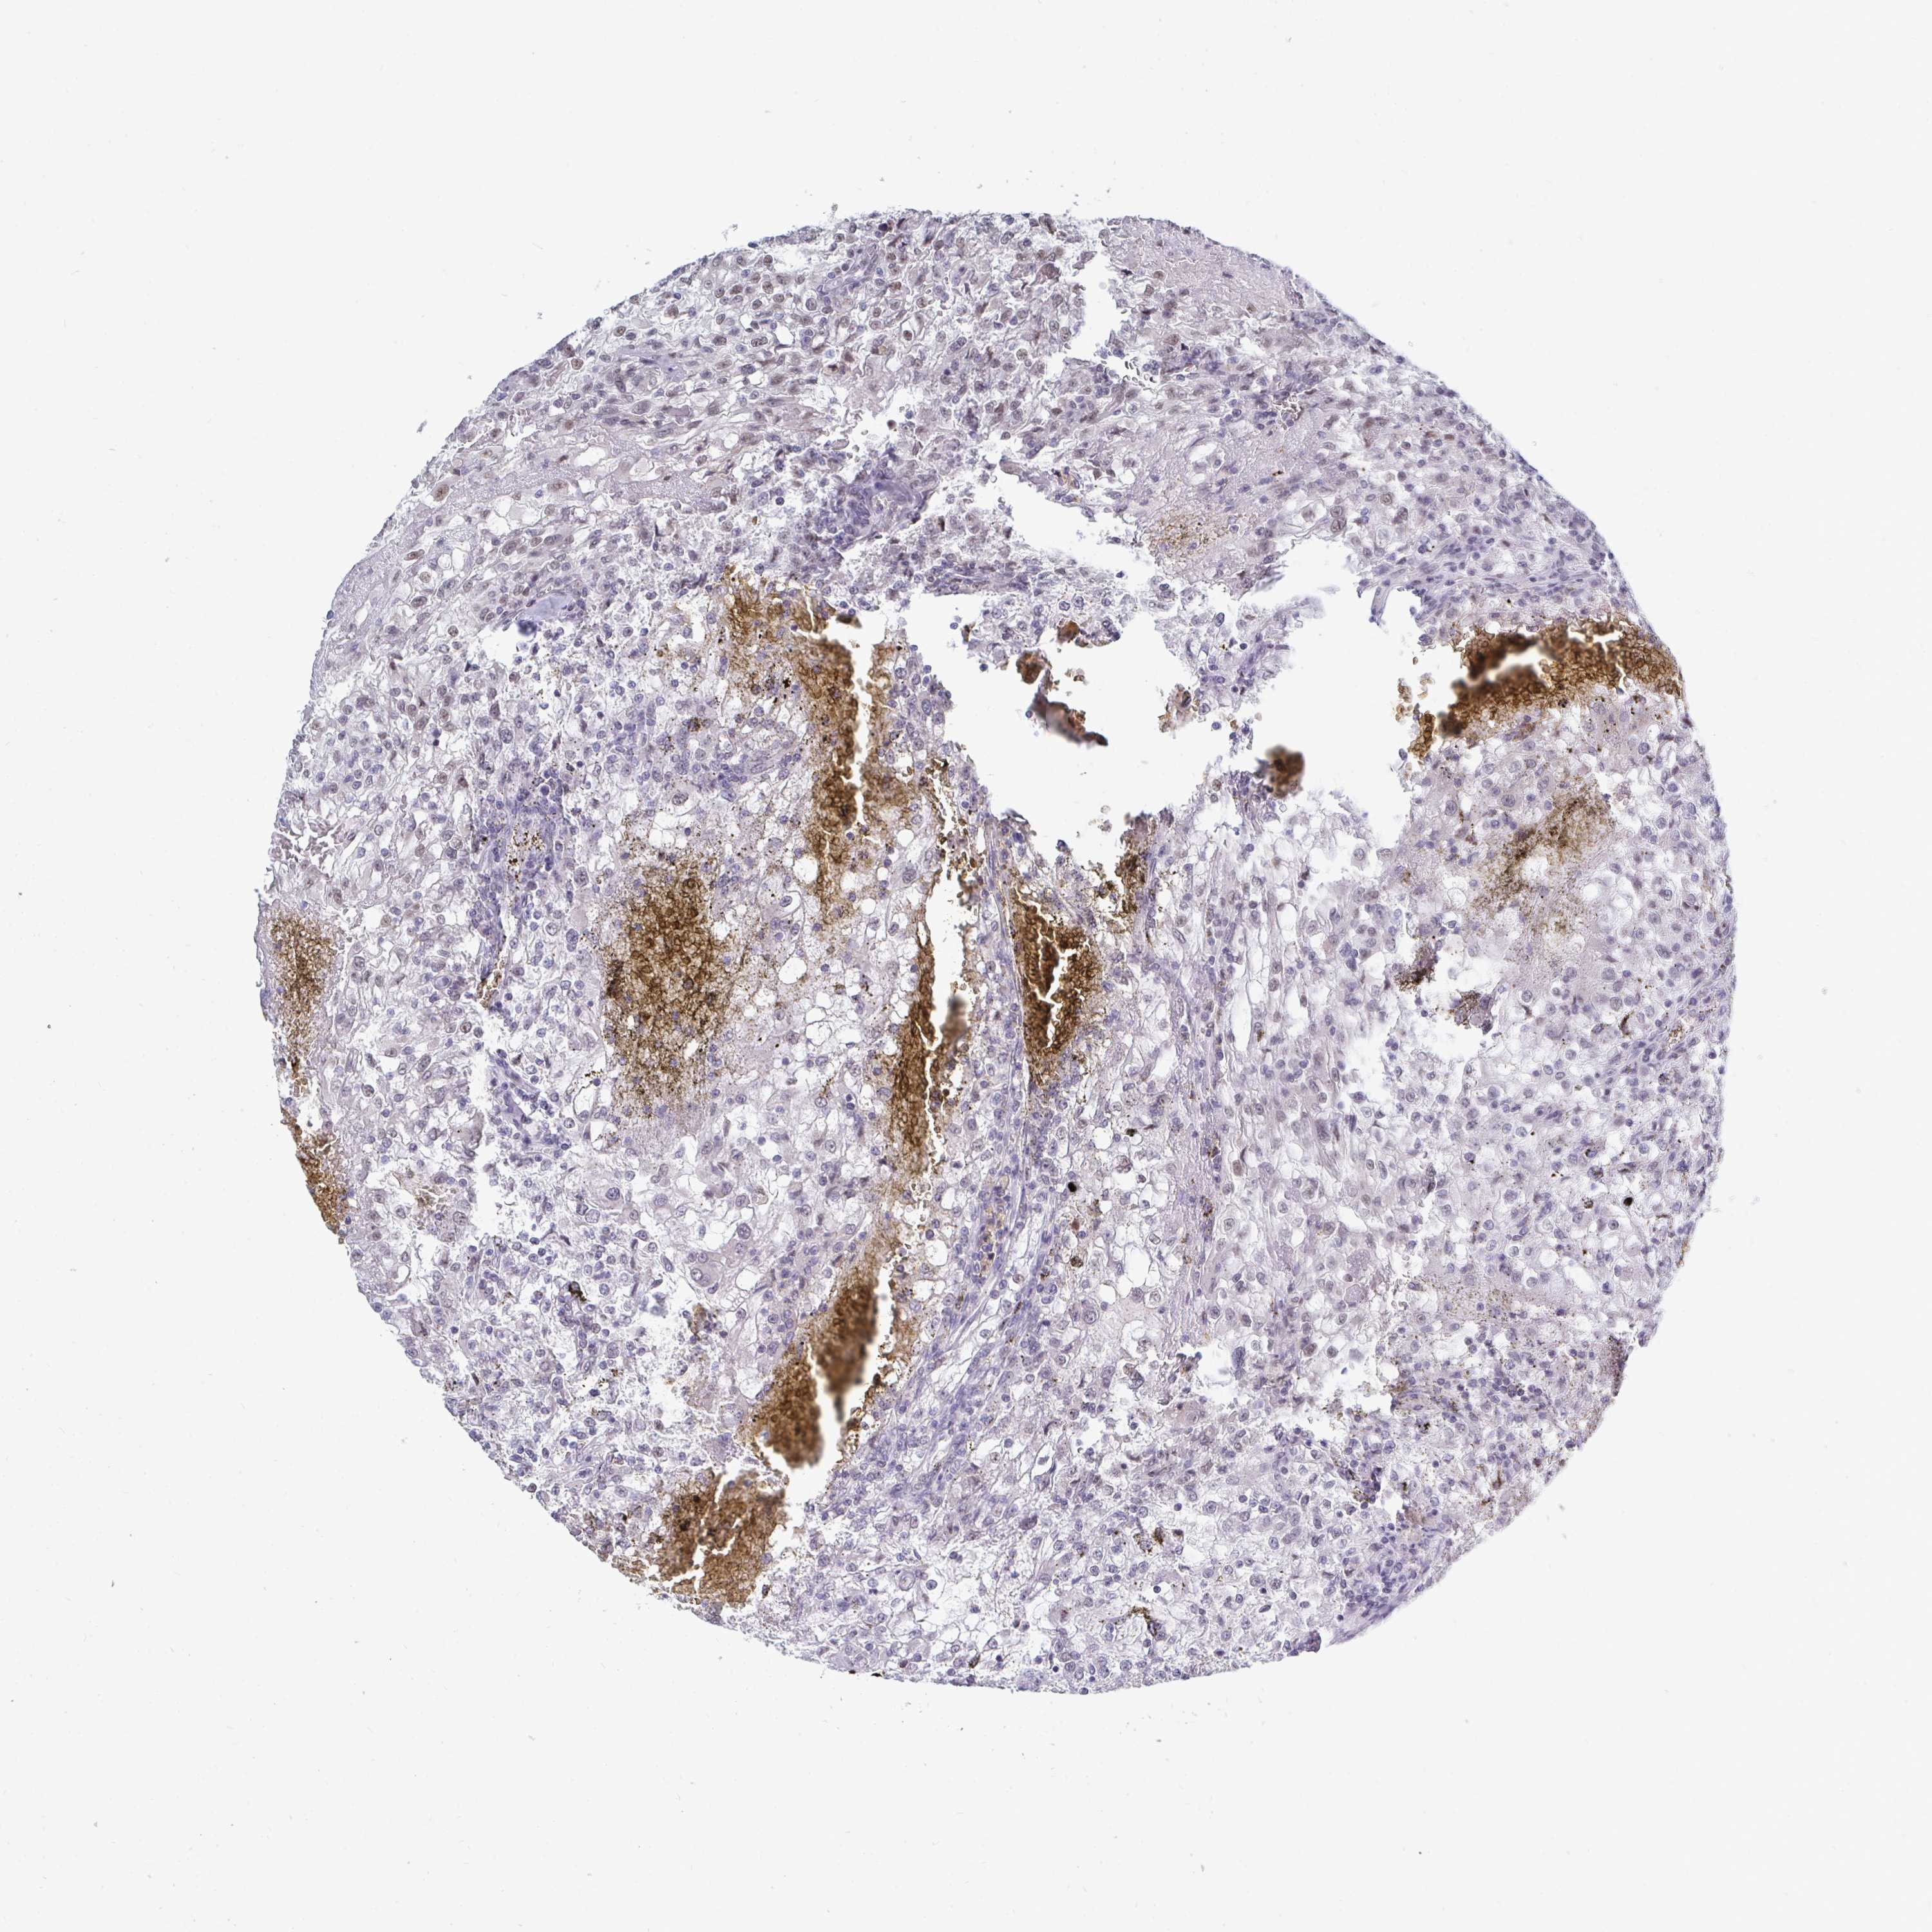

KIDNEY RENAL CLEAR CELL CARCINOMA (TCGA) - Interactive survival scatter ploti

The Survival Scatter plot shows the clinical status (i.e. dead or alive) for all individuals in the patient cohort, based on the same data that underlies the corresponding Kaplan-Meier plots. Patients that are alive at last time for follow-up are shown in blue and patients who have died during the study are shown in red.

The x-axis shows the expression levels (FPKM) of the investigated gene in the tumor tissue at the time of diagnosis. The y-axis shows the follow-up time after diagnosis (years). Both axes are complimented with kernel density curves demonstrating the data density over the axes. The top density plot shows the expression levels (FPKM) distribution among dead (red) and alive patients (blue). The right density plot shows the data density of the survived years of dead patients with high and low expression levels respectively, stratified using the cutoff indicated by the vertical dashed line through the Survival Scatter plot. This cutoff is automatically defined based on the FPKM cutoff that minimizes the p-score. The cutoff can be changed by dragging the vertical line or by entering a cutoff value in the square labeled "Current cut-off".

Under the Survival Scatter plot the p-score landscape (black curve; left axis) is shown together with dead median separation (red curve; right axis). Dead median separation is the difference in median mRNA expression between patients who have died with high and low expression, respectively. It is calculated as follows: median FPKM expression of dead patients with high expression - median FPKM expression of dead patients with low expression. This is intended to aid the user in visually exploring custom cutoffs and the associated p-scores and dead median separation.

Individual patient data is displayed and can be filtered by clicking on one or more of the category buttons on the top of the page. Categories describing expression level and patient information include: high, low, alive, dead, female, male and tumor stages. The scale of the x-axis can be toggled between linear and log-scale by clicking on the "x log" button. Mouse-over function shows TCGA ID, patient information and mRNA expression (FPKM) for each patient.

& Survival analysisi

Kaplan-Meier plots summarize results from analysis of correlation between mRNA expression level and patient survival. Patients were divided based on level of expression into one of the two groups "low" (under cut off) or "high" (over cut off). X-axis shows time for survival (years) and y-axis shows the probability of survival, where 1.0 corresponds to 100 percent.

TRIP12 is potential prognostic, high expression is favorable in Kidney Renal Clear Cell Carcinoma (TCGA)

Best expression cut offi

Based on the FPKM value of each gene, patients were classified into two groups and association between prognosis (survival) and gene expression (FPKM) was examined. The best expression cut-off refers the FPKM value that yields maximal difference with regard to survival between the two groups at the lowest log-rank P-value. Best expression cut-off was selected based on survival analysis .

When clicking on this number, the vertical dashed line indicating cut-off, the interactive survival plot, and the Kaplan-Meier curve will be adjusted to show results based on the best expression cut-off.

: 31.45

Median expressioni

Median expression refers to the median FPKM value calculated based on the gene expression (FPKM) data from all patients in this dataset. When clicking on this number, the vertical dashed line indicating cut-off, the interactive survival plot, and the Kaplan-Meier curve will be adjusted to show results based on the median expression.

: N/A

Median follow up timei

Median follow up time refers to the median time (years) after diagnosis with this type of cancer, based on clinical data from all patients in this dataset.

P scorei

Log-rank P value for Kaplan-Meier plot showing results from analysis of correlation between mRNA expression level and patient survival.

N/A

5-year survival highi

5-year survival for patients with higher expression than the expression cutoff.

For melanoma and glioma, 3-year survival is shown.

5-year survival lowi

5-year survival for patients with lower expression than the expression cutoff.

TCGA RNA samplesi

RNA-seq data is reported as average FPKM (number Fragments Per Kilobase of exon per Million reads), generated by the The Cancer Genome Atlas (TCGA) .

Normal distribution across the dataset is visualized with box plots, shown as median and 25th and 75th percentiles. Points are displayed as outliers if they are above or below 1.5 times the interquartile range. FPKM values of the individual samples are presented next to the box plot.

Average pTPM 46.4

Number of samples 521